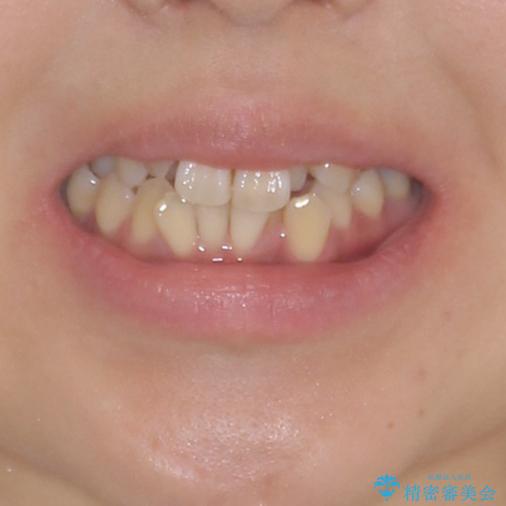

狭い上顎骨を拡大 著しい叢生を抜歯矯正で改善

- 上顎の著しい叢生と奥歯の咬みにくさを気にして来院された患者様です。

骨格的に上顎は狭く、下顎は右側にシフトしていたため、右側臼歯はクロスバイトとなっていました。